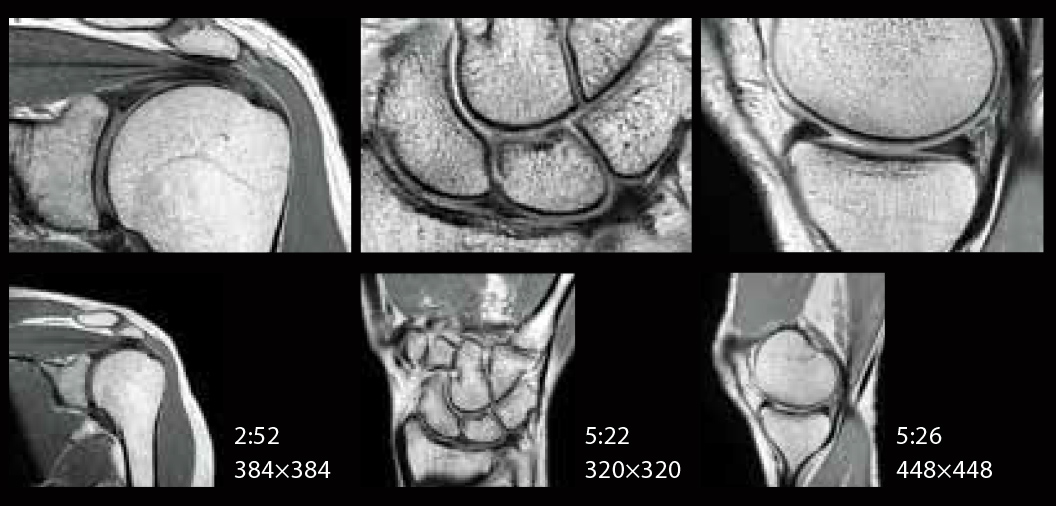

IP-RAPID hem yüksek görüntü kalitesi hem de daha kısa tarama süresi sağlar

IP-RAPID, görüntü kalitesini korurken tarama süresini azaltabilen bir teknolojidir.

Yetersiz örnekleme ve yinelemeli rekonstrüksiyonu birleştirerek, çeşitli bölge ve işlevlerle bir araya getirilebilir.

SNR ve uzamsal çözünürlük de tarama süresi korunarak iyileştirilebilir.